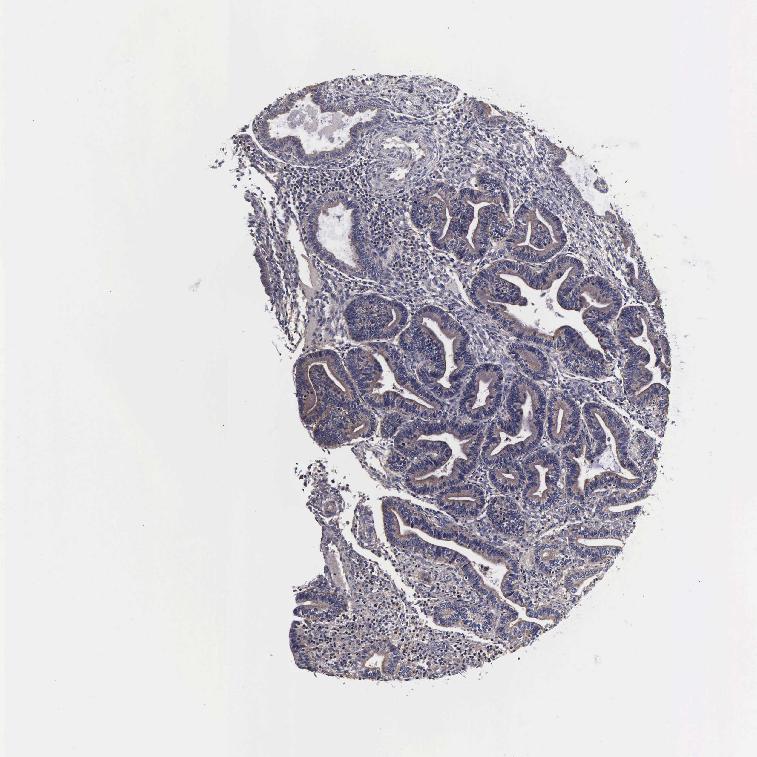

PSMA3